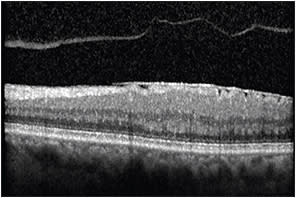

Evaluation of volume scans is important in identifying features, such as outer retinal tubulations (ORTs) in AMD. ORTs appear as round or ovoid hyper-reflective structures with a central area of hyporeflectivity (Figure 4).

Figure 4. OCT image demonstrating an ovoid hyper-reflective structure with a central area of hyporeflectivity corresponding to an outer retinal tubulation.

This configuration can be confused for intraretinal cysts, and care must be taken to differentiate these structures, especially when management depends on appropriate interpretation.

Up to 2.5% of eyes can have ORTs present at the time of diagnosis of neovascular AMD, and up to 45% of eyes showed development of ORTs by four years.7 ORTs tend to develop adjacent to areas of geographic atrophy or hyper-reflective subretinal tissue, and they appear to be predictive of slower rates of growth of GA when compared with eyes without ORTs.8